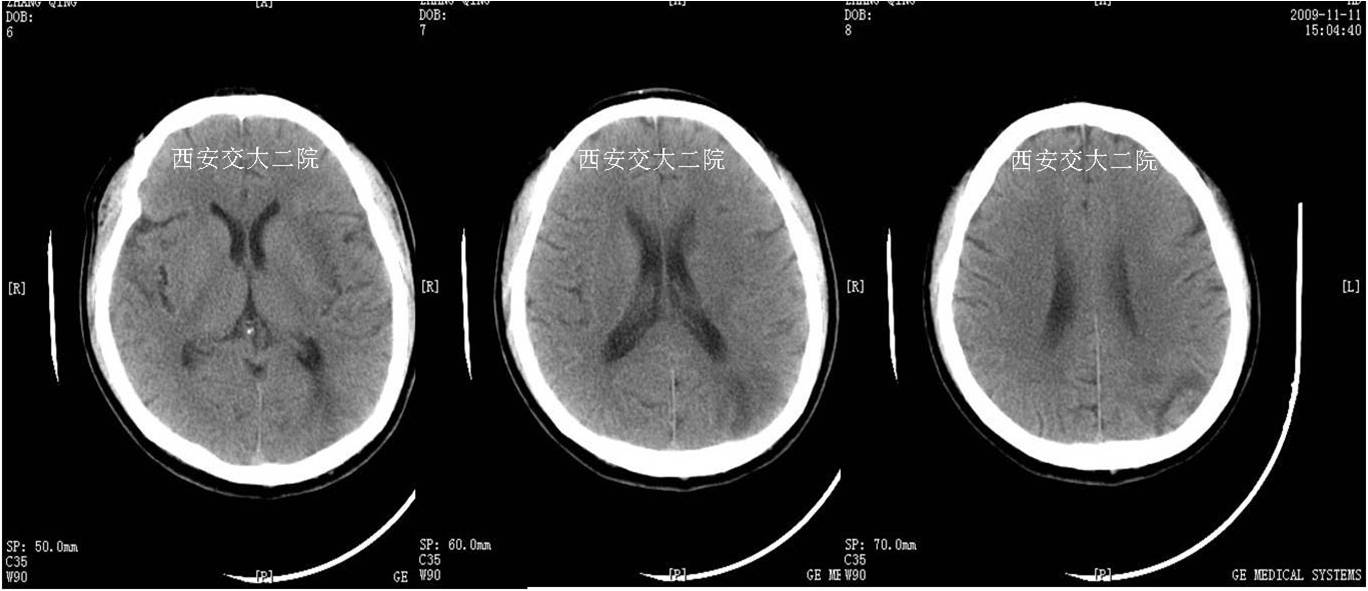

Case 1 颈内动脉C1段急性闭塞(2009年)

》男,70岁,突发右侧肢体无力3小时,DSA提示左侧颈内动脉起始段闭塞。

术前脑CT